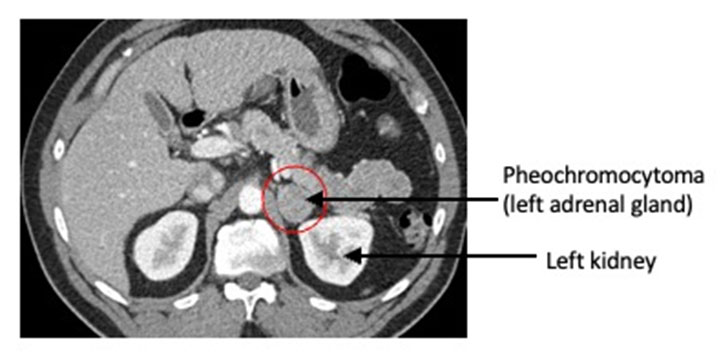

شكل ورم القواتم

من حيث الشكل، لا يمكن التعرف على الورم بالعين المجردة. يتم تحديد شكل ورم القواتم عبر التصوير الطبي مثل الأشعة المقطعية أو الرنين المغناطيسي، حيث يظهر ككتلة قد تختلف في الحجم، وقد تكون حميدة في أغلب الحالات، لكنها تظل نشطة هرمونيًا.